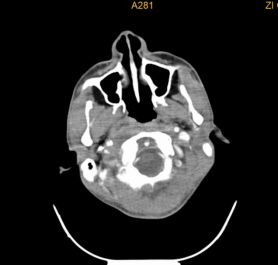

鼻咽癌发生颈淋巴结转移的概率最高,约占60%,很多患者以颈部肿块为首发症状,鼻咽癌的颈部淋巴结转移位置常常在颈深上淋巴结(大概说就是我们耳垂下方区域)。

常见的还有口咽、口腔、鼻腔鼻窦癌颈淋巴结转移、甲状腺癌颈淋巴结转移等。颈部恶性肿瘤的诊断需要借助详细的病史、全面的体格检查及辅助检查(包括彩超、CT、电子鼻咽喉镜等),最重要的还是要去耳鼻咽喉头颈外科专科就诊。